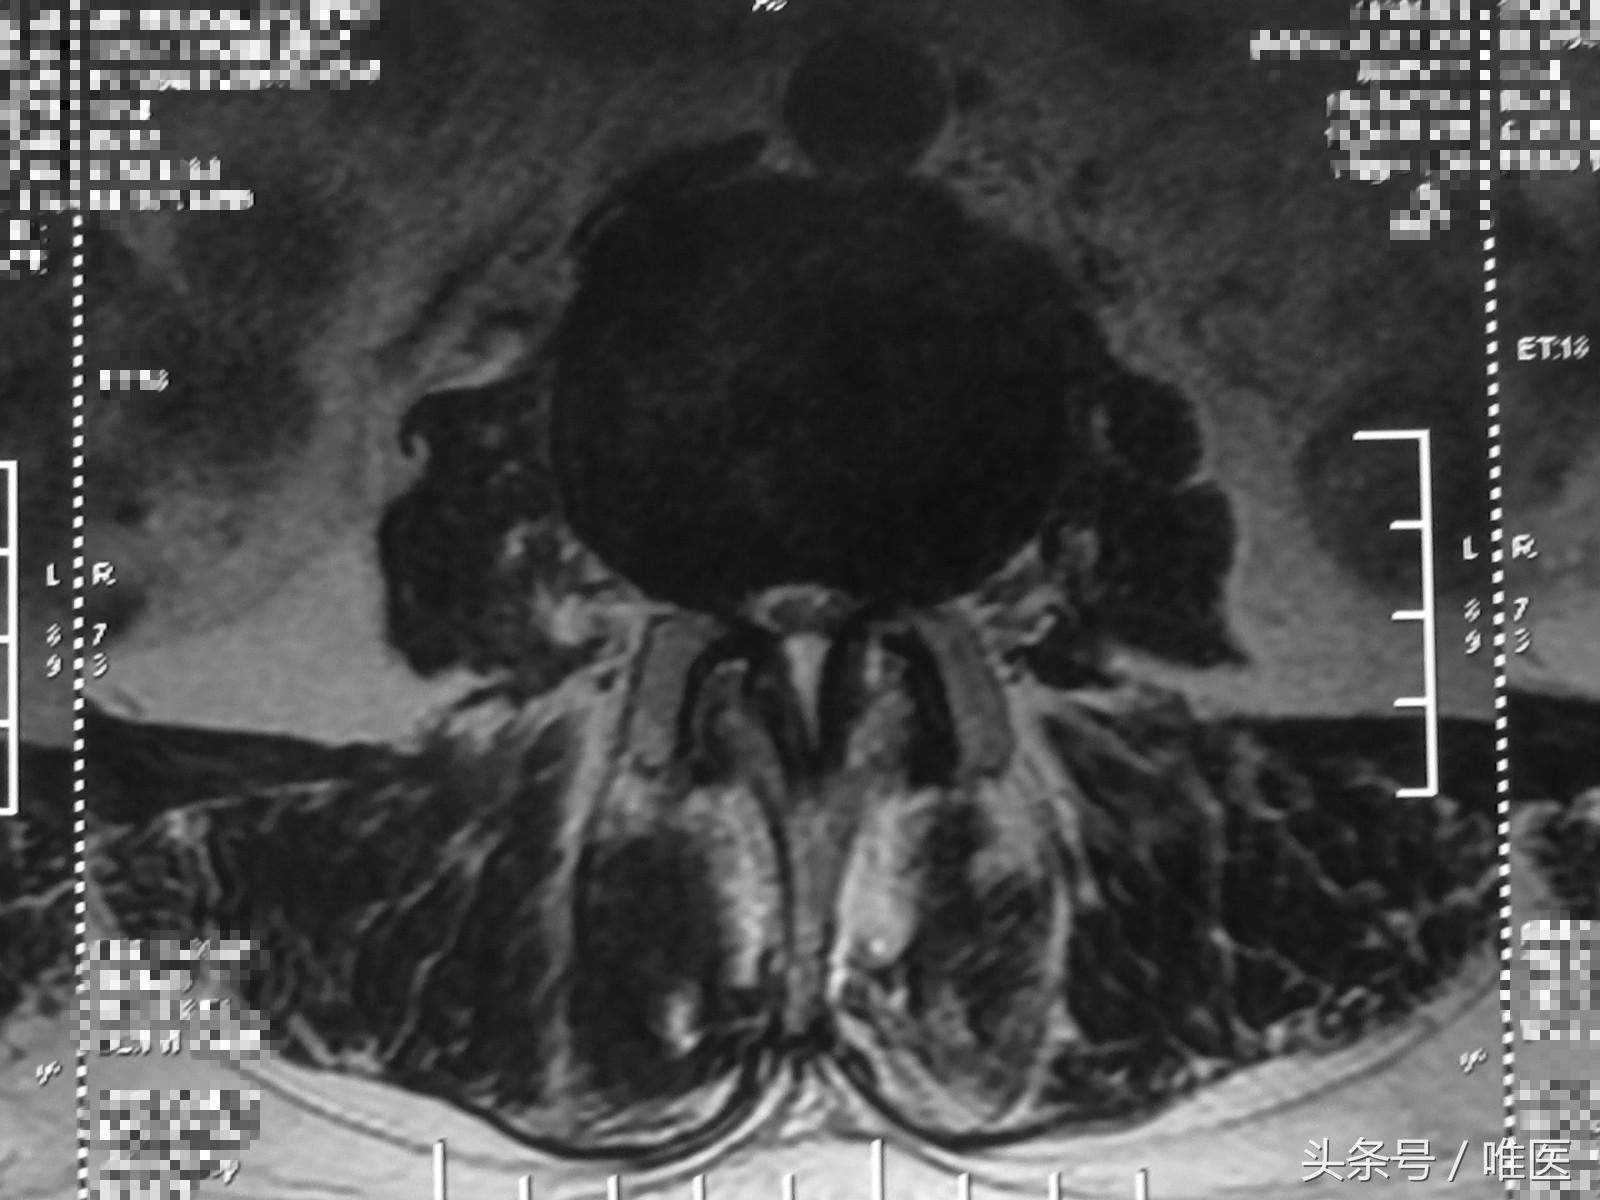

4.MRI检查

腰椎MRI检查能够清楚地显示椎管、硬膜囊外脂肪、硬膜囊、脑脊液、脊髓等结构。它对软组织成像分辨能力比CT更高,除了能够横断面扫描成像外,还能够进行矢状位的成像。但MRI价格相对昂贵,黄韧带骨化及纤维环钙化的辨识能力差。